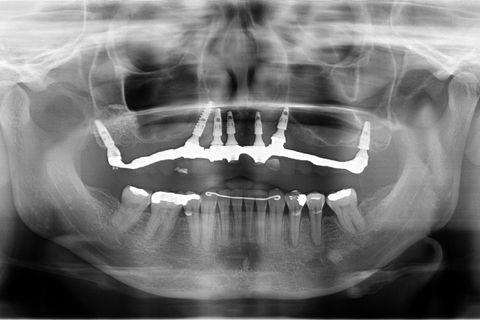

Panorâmica de controle de 2013, breve incluirei controle desse ano.

Paciente desdentada total superior, portadora de prótese total mal adaptada. Proposto para ela a instalação de 7 implantes, dos quais 5 na porção mais anterior da maxila(abordagem palatina). Foram instalados ainda dois implantes na junção pterigopalatina para eliminação de um possível cantilever produzido por enxertos de seios. O implante do lado direito precisou ser executado através de uma técnica transinusal devido ao resíduo insuficiente da tuberosidade. Nessa técnica, o trajeto entre a inserção cristal do implante e sua chegada ao pterigoide é feita levantando-se a membrana do seio maxilar e preenchendo-a com enxerto alógeno(bio-oss, no caso), sua ancoragem tem torque de inserção alto devido à densidade da junção - tal qual a técnica direta, utilizada no lado esquerdo

Follow up de 4 anos.